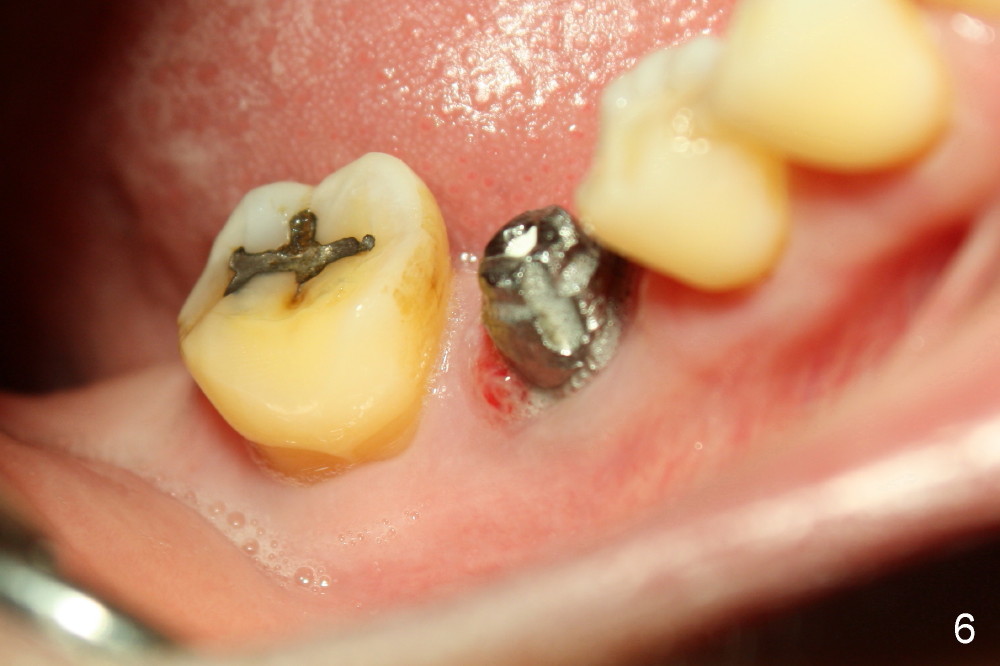

The infection may be related to chronic infection at the tooth #9. The latter is extracted, but the infection at the site of #30 does not resolve (Fig.5,6). The buccal flap is raised to reveal granulation tissue distobuccal to the implant (Fig.7). Bony defect and implant thread exposure are shown after debridement (Fig.8). Irradiated cancellous bone graft is placed to the defect (Fig. 9, Rocky Mountain Tissue Bank). The flap is closed with relative tension free. The definitive crown is temporarily cemented. The graft is exposed with no infection 2 week post grafting (Fig.10). The distobuccal defect appears to have healed 5 months post grafting (Fig.11) and the crown is permanently cemented (Fig.12). There is no buccal bone resorption, probably associated with immediate implantation. The patient remains asymptomatic 13 months postop.